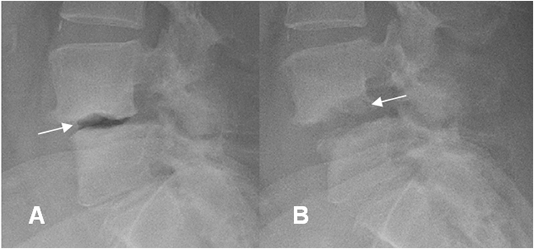

Fig 141 D. Espondilodisquitis. Tomado referencia 57.

A: Rx lateral. Fenómeno del vacío en L4-L5, por degeneración del disco.

B: Rx lateral. Desaparición del aire intervertebral y osteolisis de las placas terminales, por espondilodisquitis.